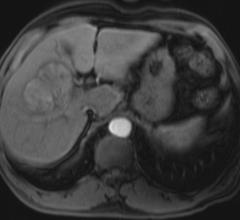

March 2, 2021 — West Virginia University scientists used magnetic resonance imaging (MRI) scans to show what happens ...